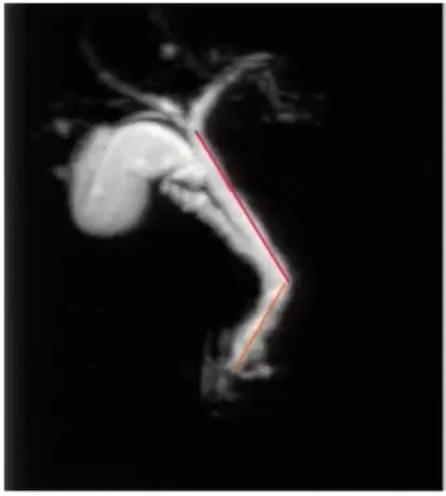

图1:腹膜后方下腔静脉处于腹主动脉左侧;左肾静脉出左肾门后,汇入下腔静脉路径缩短

下腔静脉畸形

下腔静脉畸形 以双下腔静脉畸形及左下腔静脉畸形最常见。

左下腔静脉畸形为肾下段下腔静脉在主动脉的左侧上升,与左肾静脉汇合,通过主动脉前方与右肾静脉汇合,并在此水平上形成正常的右下腔静脉。

双下腔静脉畸形表现为左下腔静脉终止于左肾静脉,通过主动脉前方汇入右下腔静脉。

临床意义:

绝大多数情况无症状,不具有临床意义; 先天性下腔静脉畸形是引起特发性深静脉血栓的高危因素之一; 对涉及心脏、肝脏、肾脏及腰膜后的手术,可能会增加手术风险。

案例分享:

图11:腹主动脉两侧均有下腔静脉影,左侧下腔静脉向上与左肾静脉汇合后,在腹主动脉前方绕行,移行为右侧下腔静脉